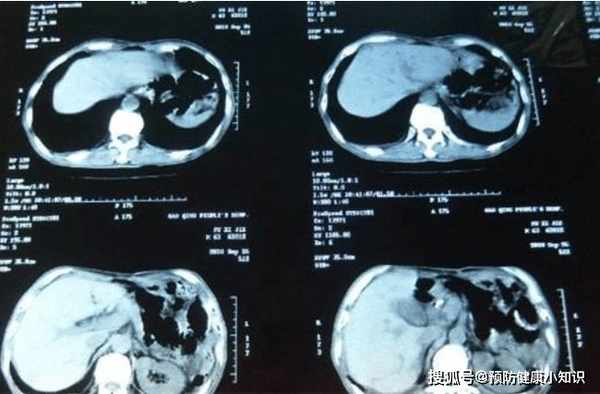

最近,楊先生經常感到身體乏力、精神萎靡,以為是沒休息好導致的,然而,沒過多久,體重持續下降,整個人看起來消瘦了很多,腹部還隱隱作痛,就到醫院進行了檢查,沒成想竟然查出了肝癌。

當楊先生聽到這個消息以後,感覺天都要塌了,不知以後該怎麼辦,比較幸運地是癌細胞還沒有轉移,治癒的可能性還比較大。